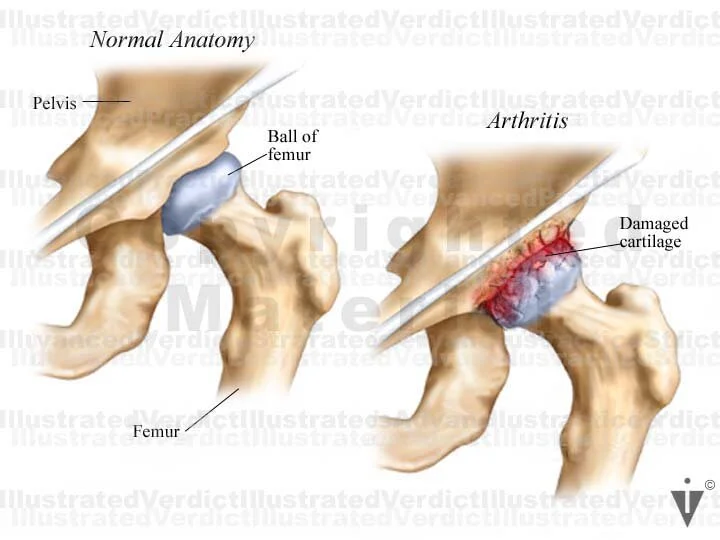

BOARD 4

1. Normal anatomy: hip joint

2. Arthritic hip joint